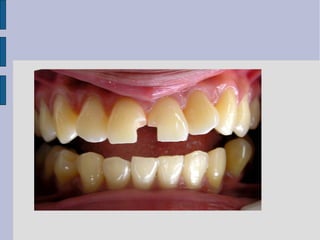

BEFORE AAFFTTEERR

Before the restoration

procedure.

After restoring with Composite

Resin Material

class iv direct composite

Class IV Tooth Preparation

 preoperative assessment of

occlusion is very important

(placement of margin in noncontact

areas)

 shade selection is more difficult

 preparation is similar to Class III

except that the preparation for class

IV is extended to the incisal angles